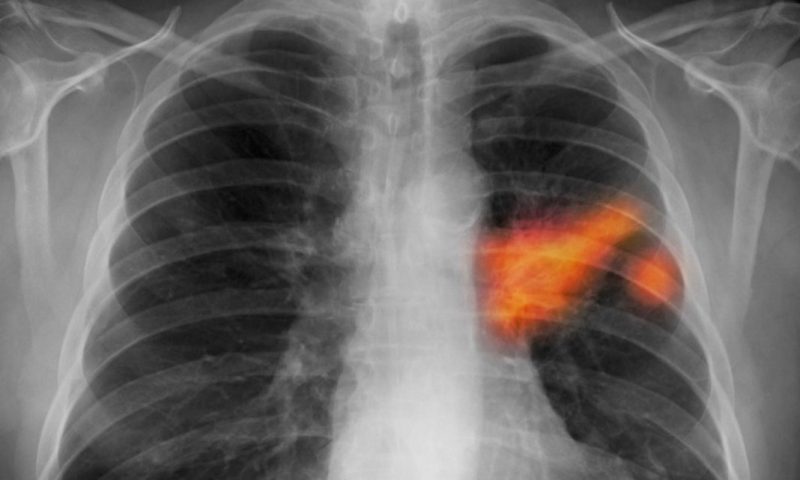

Центральная форма рака легких на снимке

Идентификация центрального рака легких возможна по целому перечню, так называемых, рентгенологических симптомов. Речь идет о дестабилизации вентиляции, инфильтрации (выглядит на снимке, как темное пятно) и компенсаторной воздушности участков, находящихся поблизости. В целом, синдромы злокачественного формирования определяются как типичные, а потому постановка диагноза не вызывает затруднений.

При центральной форме рака четко идентифицируется начальное узловое формирование (имеет бугристый контур и неоднородное строение). Присутствуют изъязвления с какой-либо из сторон. Также следует учитывать, что инфильтрация легочных тканей без начальных узлов не должна восприниматься как отсутствие онкологии. При диагностировании центральной формы рака легких следует обратить внимание на то, что:

При центральном типе рака на рентгене видны такие изменения, как затемнение, отсутствие какой-либо разницы между границей кардии и диафрагмы. Помимо этого, идентифицируется изменение, связанное с положением диафрагмы и сердечной мышцы. Это касается начальной формы, в то время как на более поздних этапах не заметить значительный по своим размерам опухолевый узел просто невозможно.

Затемненный узел может характеризоваться различной величиной и формой. В случае расположения пятнышка на периферии, ему характерна овальная форма. В некоторых ситуациях тень узла с непропорциональной формой может располагаться вблизи от средостения. О том, что рентген легких в этом случае точно определил злокачественное новообразование легких, свидетельствуют некоторые признаки:

В случае развития экзобронхиального новообразования, на рентгенограмме будут очевидны другие признаки: бугристые узловые формирования в прикорневой области, лучистые контуры (так называемый синдром «восходящего солнца»). Кроме того, патология ассоциируется со стандартными признаками: гиповентиляция, сужение бронхиального просвета и увеличение размеров корневых лимфатических узлов.